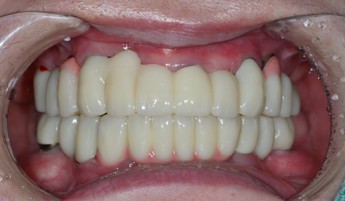

전체 치아를 상실했을 때전악 임플란트

전악 임플란트는 치아가 전혀 없거나 심한 구강 질환이 있을 때도

전체 보철물을 제작하고 임플란트를 잇몸 뼈에 식립하여

자연치아와 거의 같은 기능과 미용 효과를 되살려 줍니다.